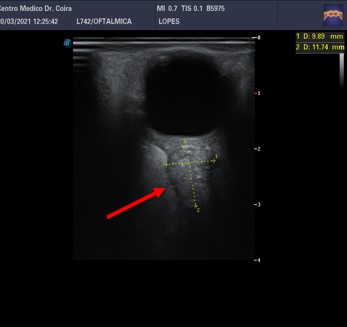

Imágenes E y F: ecografía ocular derecha: a nivel retroorbitario en el ojo derecho y en el área correspondiente a la inserción del nervio óptico, se observa una imagen asimétrica con relación al contralateral de ecoestructura sólida ubicada en la vaina del nervio óptico las medidas 11,7 x 9,8 mm.